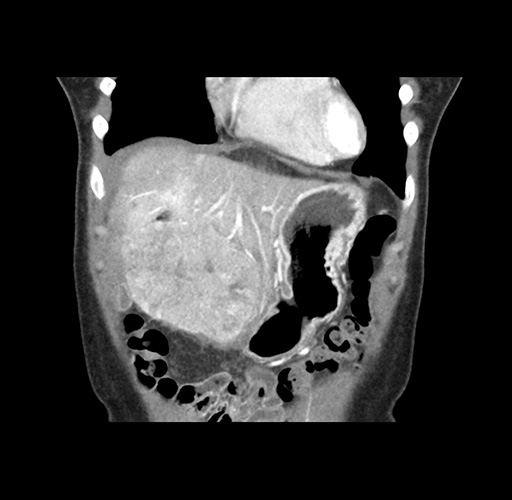

Imaging Analysis

Look through the patient's CT scan to identify any areas of concern for the necessary procedure.

Based on your CT findings, which issue(s) would give reason for "planned slowing down moment(s)" in this case?